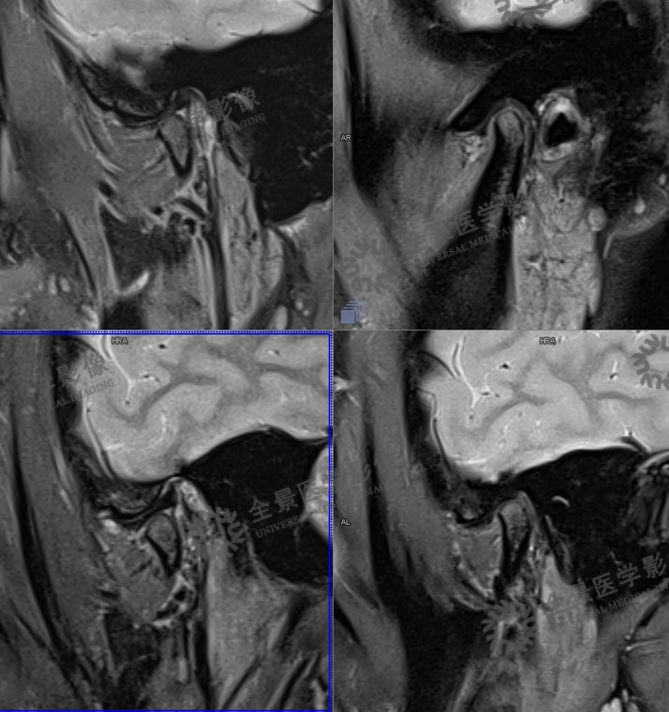

一、颞颌磁共振检查

MRI:可清楚、全面地反映关节结构及附件组织的变化。MR动态电影能够很好地显示关节盘、髁状突的运动情况

颞颌磁共振检查